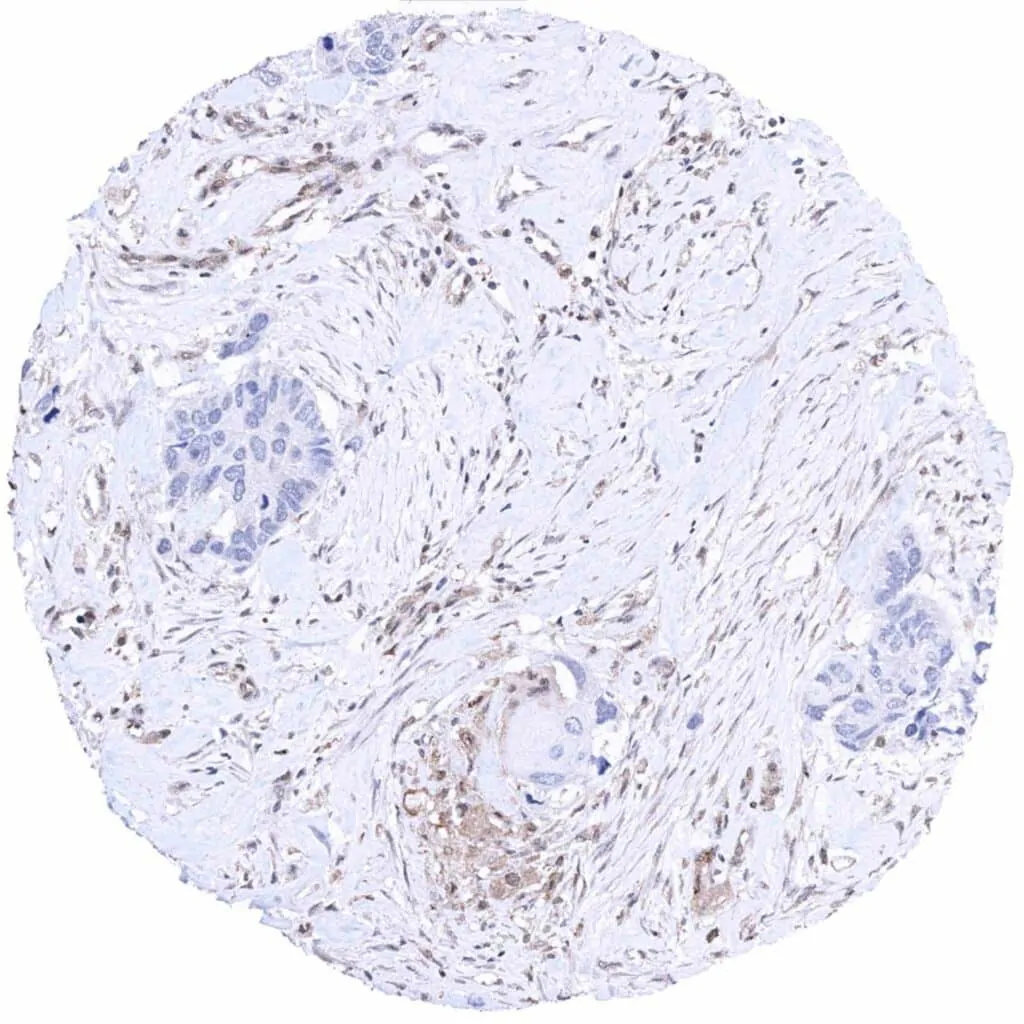

Prostate – Adenocarcinoma (Gleason 4+4=8) with complete absence of MTAP staining in tumor cells. Intense MTAP staining of inflammatory and stromal cells